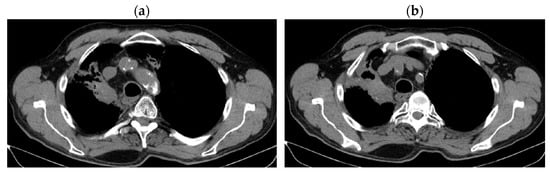

2. Case Presentation

2.1. Systemic Third-Line Therapy (4xDocetaxel) Was Initiated 04–07/2020

2.2. Monitoring 2022: Oncological Commission 1910/16.08.2022

2.3. Oncological Committee 07/25/2023 Recommended